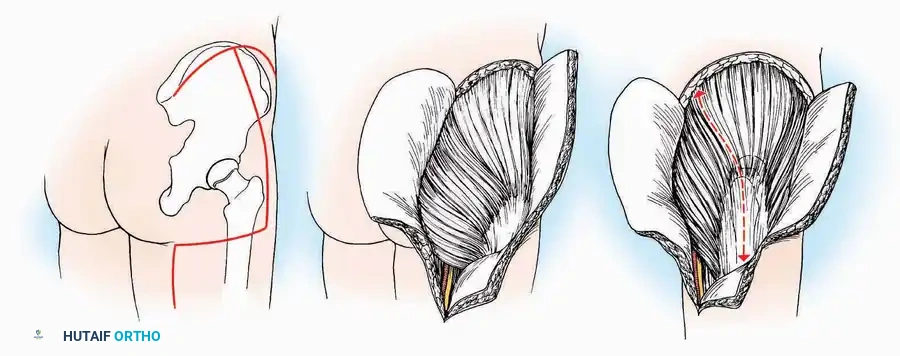

SURGICAL APPROACHES TO THE CALCANEUS

Approaches to the calcaneus are dictated by the pathology—trauma (intra-articular fractures) versus tumor/infection. Positioning is critical; while the prone position offers excellent bilateral access, the lateral decubitus or modified supine positions are more frequently utilized for unilateral trauma.

Lateral Approach (Extensile Lateral)

This is the workhorse approach for open reduction and internal fixation (ORIF) of displaced intra-articular calcaneal fractures.

Indications: ORIF of calcaneus fractures, lateral wall exostectomy, subtalar arthrodesis.

Positioning: Lateral decubitus with the operative leg up, or supine with a large bump under the ipsilateral hip to internally rotate the leg.

Surgical Technique:

* Incision: Begin the incision on the lateral margin of the Achilles tendon near its insertion. Extend it distally to a point 4 cm inferior and 2.5 cm anterior to the lateral malleolus. (For trauma, a classic L-shaped extensile incision is often used, dropping straight down anterior to the Achilles, then curving gently toward the base of the 5th metatarsal).

* Superficial Dissection: Divide the superficial and deep fasciae. It is imperative to create a "full-thickness" flap containing skin, subcutaneous fat, and periosteum to prevent flap necrosis.

* Nerve Protection: The sural nerve crosses the proximal and distal limbs of this approach. It must be identified and protected within the anterior flap.

* Deep Dissection: Isolate the peroneal tendons (longus and brevis). Incise and elevate the periosteum below the tendons to expose the lateral wall of the calcaneus.

* Tendon Management: If severe deformity or infection is present, the peroneal tendons may be divided via Z-plasty and repaired at the conclusion of the case, though this is rarely necessary in modern fracture care.

Medial Approach

Indications: Fixation of sustentaculum tali fractures, medial process fractures, or excision of medial tarsal coalitions.

Positioning: Supine with the hip externally rotated and knee flexed (figure-of-four position).

Surgical Technique:

* Incision: Begin 2.5 cm anterior and 4 cm inferior to the medial malleolus. Carry it posteriorly along the medial surface of the foot toward the Achilles tendon.

* Superficial Dissection: Divide the fat and fascia to define the inferior margin of the abductor hallucis muscle.

* Deep Dissection: Mobilize the abductor hallucis muscle belly and retract it dorsally to expose the medial and inferomedial aspects of the calcaneal body.

* Plantar Exposure: Continue distally by dividing the plantar aponeurosis and the muscular attachments to the calcaneus, or strip them subperiosteally with an osteotome.

* Neurovascular Warning: Meticulously identify and protect the medial calcaneal nerve and the nerve to the abductor digiti minimi (first branch of the lateral plantar nerve), which are highly vulnerable during inferior retraction.

U Approach

Indications: Extensive plantar fasciotomy, radical tumor resection, or complex osteomyelitis debridement requiring access to the entire plantar surface of the calcaneus.

Positioning: Prone, with the leg supported on a large sandbag.

Surgical Technique:

* Incision: Join the medial and lateral approaches described above to form a large, continuous U-shaped incision around the posterior four-fifths of the calcaneus.

* Flap Elevation: Deepen the incision directly to bone. Elevate a massive plantar flap consisting of skin, the specialized fatty heel pad, and the plantar fascia. Retract this flap distally to expose the entire plantar calcaneal tuberosity.

Kocher Approach (Curved L)

Indications: Complete excision of the calcaneus (calcanectomy) for malignant tumors or recalcitrant osteomyelitis.

Surgical Technique:

* Incision: Incise the skin over the medial border of the Achilles tendon, starting 7.5 cm proximal to the calcaneal tuberosity. Extend it distally to the inferoposterior aspect of the tuberosity, curve it transversely around the posterior heel, and continue distally along the lateral surface of the foot to the tuberosity of the fifth metatarsal.

* Deep Dissection: Divide the Achilles tendon directly at its insertion and carry the dissection down to the bone.

* Enucleation: To reach the superior surface, free all tissues beneath the severed Achilles tendon. The calcaneus can then be enucleated subperiosteally or extraperiosteally depending on the oncologic or infectious margins required.